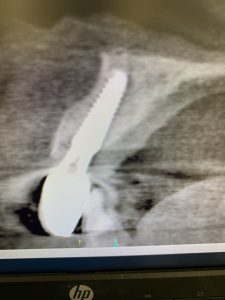

本日は朝から理事長のソケットリフトオペが。

確実に難なく30分で終了!

肥厚してる上顎洞(副鼻腔)内粘膜である為、リフトアップする形状が煙突状になりやすい症例です💦インプラント体を安定させる為に上顎洞内の粘膜を裾野広げる意識で挙げていきます。薄い膜を破かないようにドーム状に!